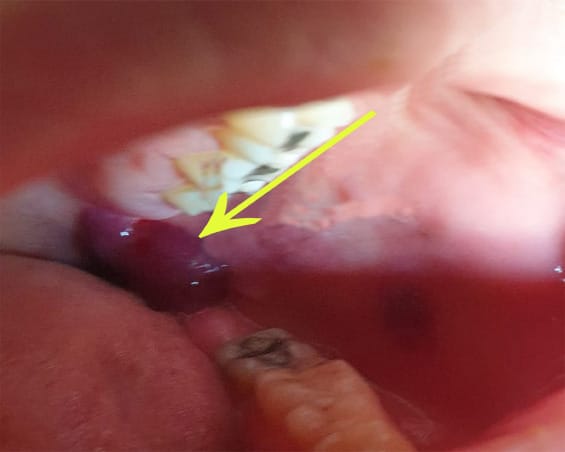

A middle-aged female patient came to the College of Dentistry, Taibah University, Saudi Arabia, 5 days after the second dose of the COVID-19 Pfizer vaccine, complaining of large, red-colored bullae at the left retromolar area (Figure 1) that ruptured and refilled.

Fig. 1 Large, deep-red bullae at retromolar area. Fig. 2 Large oral ulcerations at labial mucosa with yellow crust at lower lip. Fig. 3 Multiple large oral ulcerations at buccal mucosa.

The patient reported that she had taken the second dose of the BNT162b1 SARS-CoV-2 vaccine 5 days previously. The patient reported that she had a mild fever and general weakness. A D-dimer test was done to detect the possibility of blood clots. Laboratory examination of the D-dimer test showed a slight elevation with 0.63 mg/L.